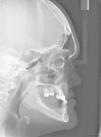

Clinical examination revealed hypohidrosis, with dry, delicate skin, decreased lachrymal secretion, scarce and very fine hair, eyelashes and eyebrows (hypotrichosis), prominent lips and nasal bridge, prominent forehead, presence of peri-oral and peri-orbitary wrinkles, periorbital and peri-oral hyperpigmentation, small sized nose with nostril hypoplasia (Figure 1).

The patient was subjected to initial X-ray assessment, panoramic X-rays were taken as well as maxillary full occlusal computerized X-rays (Figures 2-4). Radiographic assessment revealed multiple tooth ageneses. Additionally to teeth observed at the intra-oral examination, erupting upper canines (right and left) were present, as well as a tooth bud at the level of the first upper left premolar; erupting lower canines were equally present, both with possibility of crown shaped alterations; generalized bone resorption was observed in both arches.